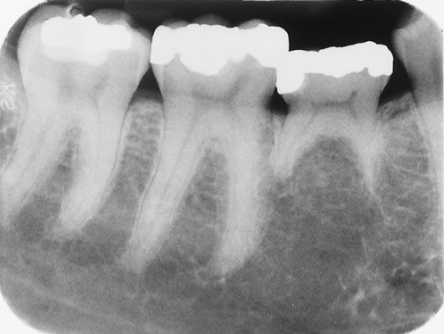

Select the most appropriate term for the anomaly associated with the 1st molar.

diastema

concrescence

dilaceration

List the anomalies seen in this radiograph of the 3rd molar region.

Impacted 2nd molar and microdontic 3rd molar

Impacted 3rd molar and supernumerary 4th molar

Impacted 2nd molar; microdontic, impacted 3rd molar; and dilacerated mesial root of the 2nd molar

Impacted 3rd molar; impacted, supernumerary 4th molar; and dilacerated mesial root of the 2nd molar